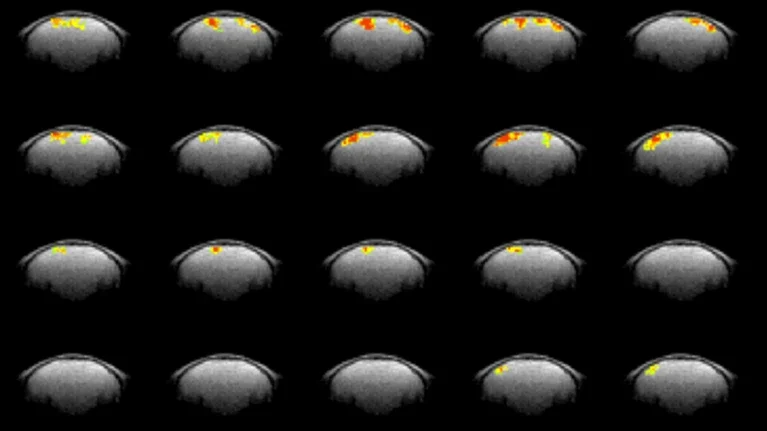

这项新技术名为神经元活动直接成像(DIANA),其工作原理是对传统的MRI机器进行改造,以更快的速度,在毫秒级别生成一系列局部图像。这一速度相当于思维的速度,神经信号传递在毫秒级别,整个认知、决策等活动只需要0.1秒。然后,研究人员将这些局部图像拼接在一起,以获得每个时间点的大脑横截面的完整视图。

为了看看他们是否可以通过这种方法识别大脑活动的任何信号,研究人员将麻醉的老鼠放入MRI扫描仪中,然后用电流轻轻敲击其面部的胡须垫。他们发现,在电击后25毫秒左右,他们的技术产生的图像在体感皮层(感知胡须刺激的小鼠大脑部分)中记录了某种信号。

进一步探索发现,DIANA信号实际上随着时间的推移而移动。它在敲击胡须垫后大约10毫秒出现在称为丘脑的大脑区域,在大约25毫秒时移动到体感皮层的一个部分,然后在几毫秒后在体感皮层的另一部分出现。